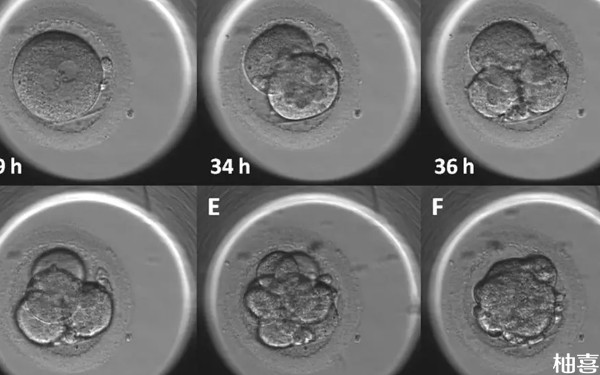

试管三代囊胚质量不好筛查活检过关率并不是很高,如果胚胎质量较好,胚胎的生长速度和发育程度都比较理想,那么胚胎活检的通过率就会相对较高,可能在80%以上。另外要注意,三代试管胚胎活检的通过率还与实验室技术有关,毕竟胚胎活检是一项技术难度较大的操作,需要有丰富经验的医生和先进的设备才能保证高的成功率。

只是有一点要注意,胚胎活检的通过率并不代表成功怀孕的概率,因为胚胎活检只是评估胚胎的基因状况,不能保证植入后的成功率和胚胎的生长发育。同时,胚胎活检也存在一定的风险,如可能对胚胎造成伤害,导致胚胎质量下降,或者出现误诊的情况。